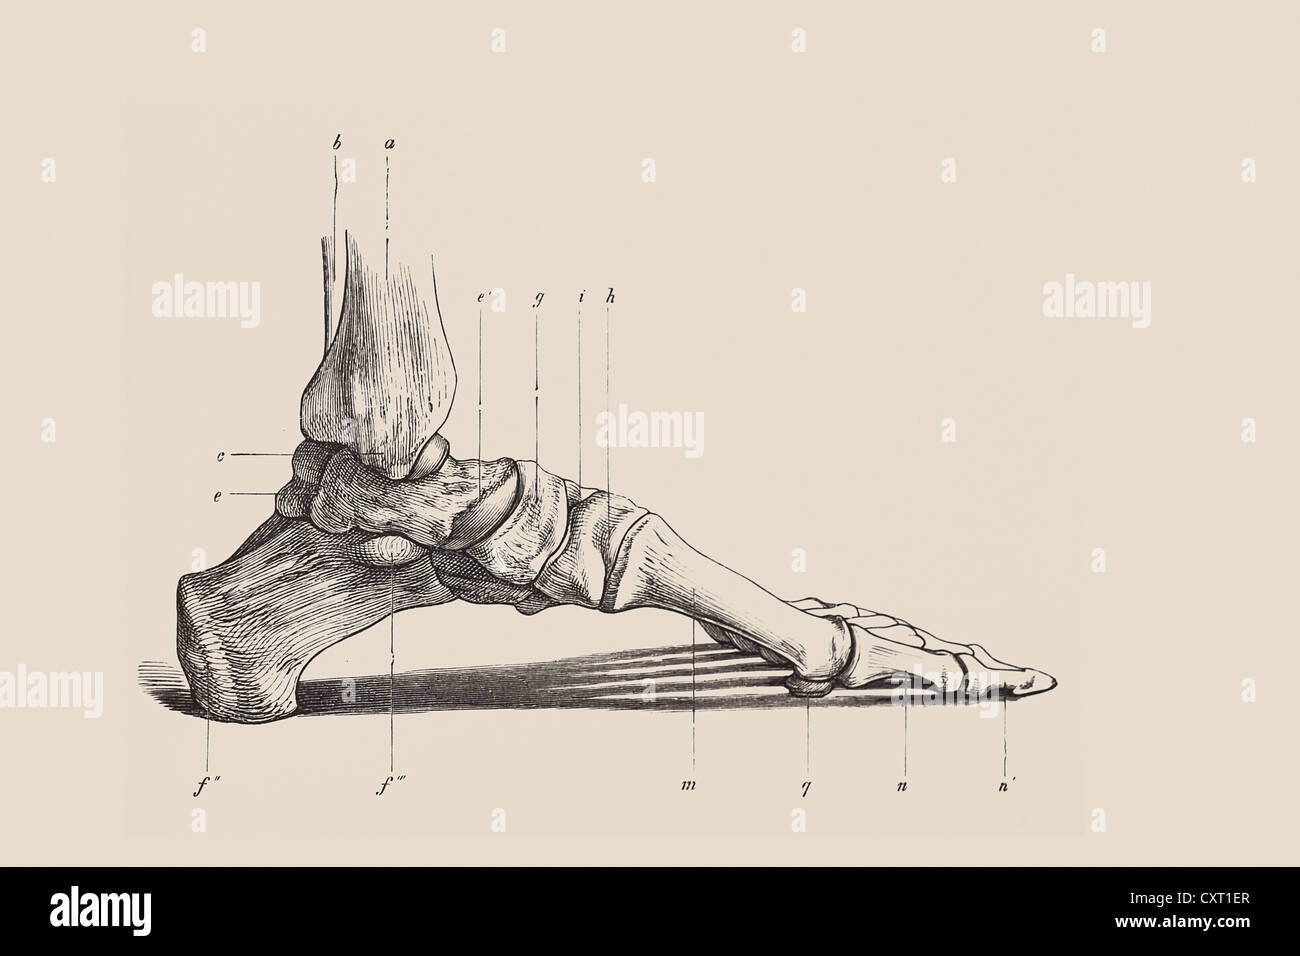

RF2R3WKY1–Illustration médicale des principales parties des os du pied en vue latérale, avec annotations.